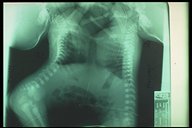

Thoracopagus twins with omphalocle

Humanogram revealed the joining of lower thorax and upper abdomen in this thoracopagus twins